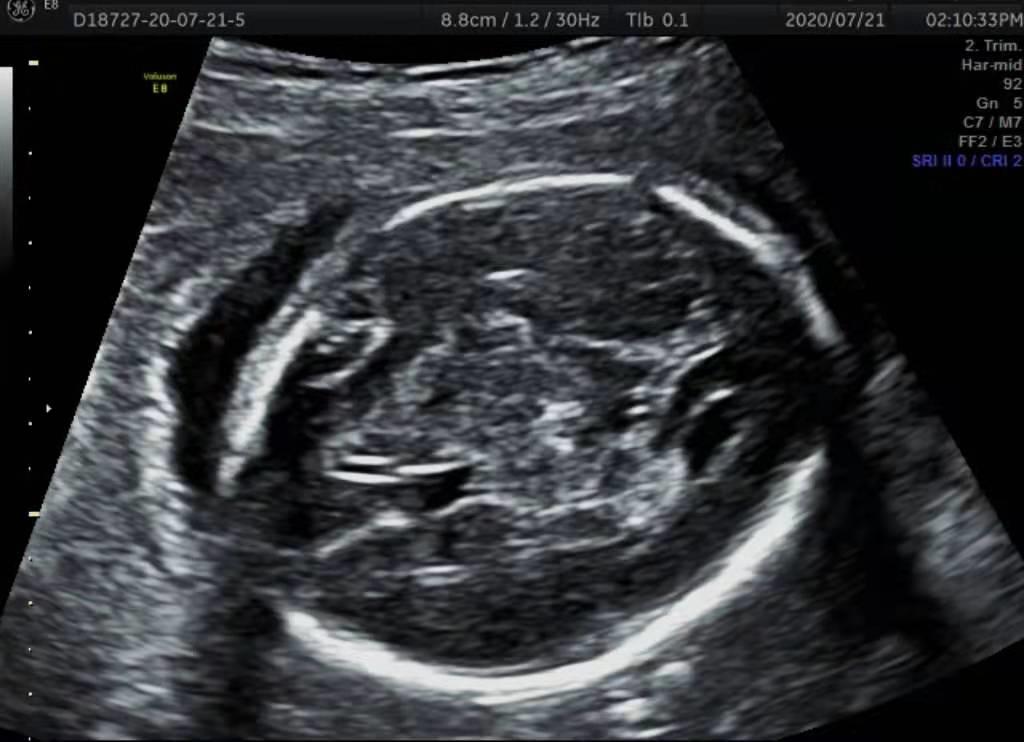

二维超声是这样的:

在超声科医生的日常工作中,所有超声检查都是在二维超声基础上进行的。比如胎儿的颅内结构检查、是否有唇裂、肢体的长短、发育以及胸腹腔内结构等等,都是经过二维超声来进行检查的。

三者中二维超声的分辨率更高,对胎儿结构畸形的判断能力高于三维和四维,因此二维图像是判断胎儿有无畸形的基本依据。

在孕中期做胎儿大畸形筛查时,即使所做的是三维、四维超声,超声医生大部分时间还是通过二维图像去识别脏器内部结构的异常。